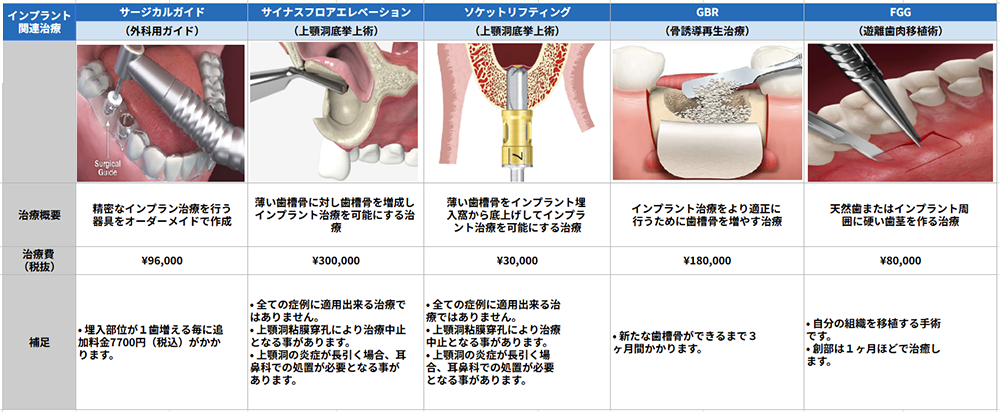

歯周病関連治療一覧表

インプラント関連治療一覧表